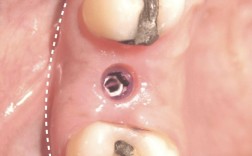

- 戴愈合帽(可选): 在某些情况下,医生可能会在基台顶部暂时戴一个小的“愈合帽”,保护基台并引导牙龈愈合形态,更常见的是直接连接最终基台(如果计划在基台连接后不久就取模制作牙冠)。

- 形成牙龈袖口: 在基台周围,医生会精心塑形牙龈组织,使其紧密地包裹住基台,形成一个类似天然牙牙龈的“袖口”结构,这对于美观、清洁以及防止食物残渣进入种植体周围至关重要。